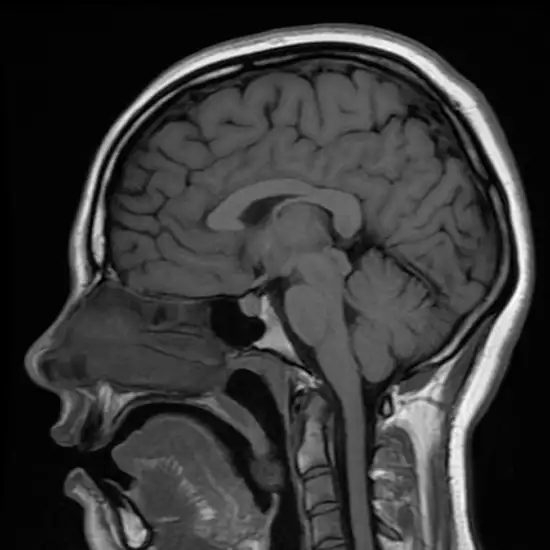

The pituitary gland is a small and bony nook gland located at the base of the skull. CECT (Contrast-Enhanced Computed Tomography) Pituitary Gland Axial or Coronal is an imaging procedure that creates different views of the pituitary gland such as axial (top and bottom view) or coronal (front and back view). This scan is used to diagnose problems/abnormalities in the pituitary gland.